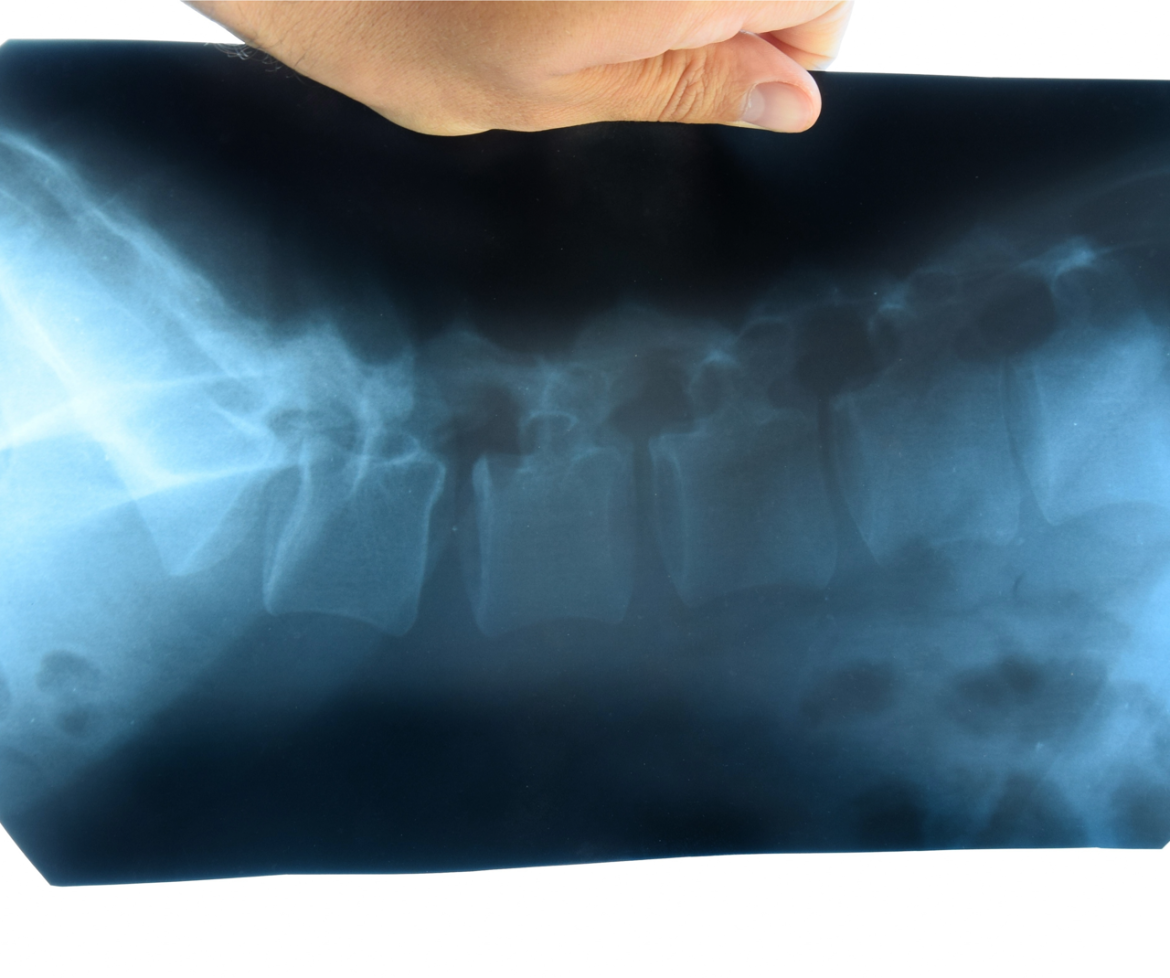

Roma, 6 dic. (Adnkronos Salute) – I pazienti affetti da spondilite anchilosante, nota anche come spondiloartrite assiale radiografica (r-axSpA), trattati con bimekizumab, un inibitore di IL-17A e IL-17F, hanno mostrato miglioramenti sostenuti in termini di segni, sintomi, attività di malattia, funzionalità fisica e qualità della vita correlata alla salute, fino a 5 anni, con un profilo di sicurezza costante per tutto il periodo di trattamento. Sono i dati a lungo termine dello studio Be-Agile di Fase 2b su bimekizumab e della sua estensione in aperto (Ole) diffusi da Ucb, azienda biofarmaceutica in occasione dell’American College of Rheumatology (Acr) Convergence 2023, svoltosi recentemente a San Diego. La spondiloartrite assiale (axSpA) – riferisce una nota – è una malattia infiammatoria cronica, immuno-mediata che colpisce principalmente la colonna vertebrale e le articolazioni che collegano il bacino e la colonna vertebrale inferiore (articolazioni sacroiliache). Il sintomo principale, nella maggior parte dei pazienti, è il dolore infiammatorio alla schiena, che migliora con l’esercizio fisico, ma non con il riposo. Altre caratteristiche cliniche comuni includono spesso uveite anteriore, entesite, artrite periferica, psoriasi, malattia infiammatoria intestinale e dattilite. L’esordio dell’axSpA avviene solitamente prima dei 45 anni. “Le persone affette da spondilite anchilosante – afferma Emmanuel Caeymaex, Executive Vice President, Immunology Solutions and Head of U.S. di Ucb – in molti casi non raggiungono un controllo a lungo termine della malattia, hanno” quindi “necessità di ulteriori opzioni terapeutiche. I dati a 5 anni di bimekizumab hanno dimostrato miglioramenti sostenuti in diversi ambiti della malattia e un profilo di sicurezza coerente con le osservazioni precedenti”.”Questo – spiega Atul Deodhar, professore di Medicina, Oregon Health & Science University, Divisione di Artrite e Malattie Reumatiche di Portland – è il primo rapporto sulle risposte Asas40 – una risposta di miglioramento del 40% secondo i criteri dell’Assessment of Spondyloarthritis International Society – a 5 anni, in pazienti con spondilite anchilosante, ad avere utilizzato un’analisi conservativa di imputazione dei non-responder. Utilizzando questo metodo, i dati hanno dimostrato che almeno la metà dei pazienti trattati con bimekizumab ha ottenuto miglioramenti duraturi nel corso dei 5 anni di trattamento”.Nell’Unione Europea bimekizumab è approvato per il trattamento della psoriasi a placche da moderata a grave negli adulti candidati alla terapia sistemica, per il trattamento dell’artrite psoriasica attiva, da solo o in combinazione con metotrexato, negli adulti che hanno avuto una risposta inadeguata o che sono stati intolleranti a uno o più farmaci antireumatici modificanti la malattia. Un’altra indicazione per bimekizumab nell’UE è il trattamento di adulti con spondiloartrite assiale attiva non radiografica, con segni oggettivi di infiammazione, come indicato dall’innalzamento della proteina C reattiva e/o dalla risonanza magnetica, che hanno risposto in modo inadeguato o sono intolleranti ai farmaci anti-infiammatori non steroidei, e per il trattamento di adulti con spondilite anchilosante attiva che hanno risposto in modo inadeguato o sono intolleranti alla terapia convenzionale.